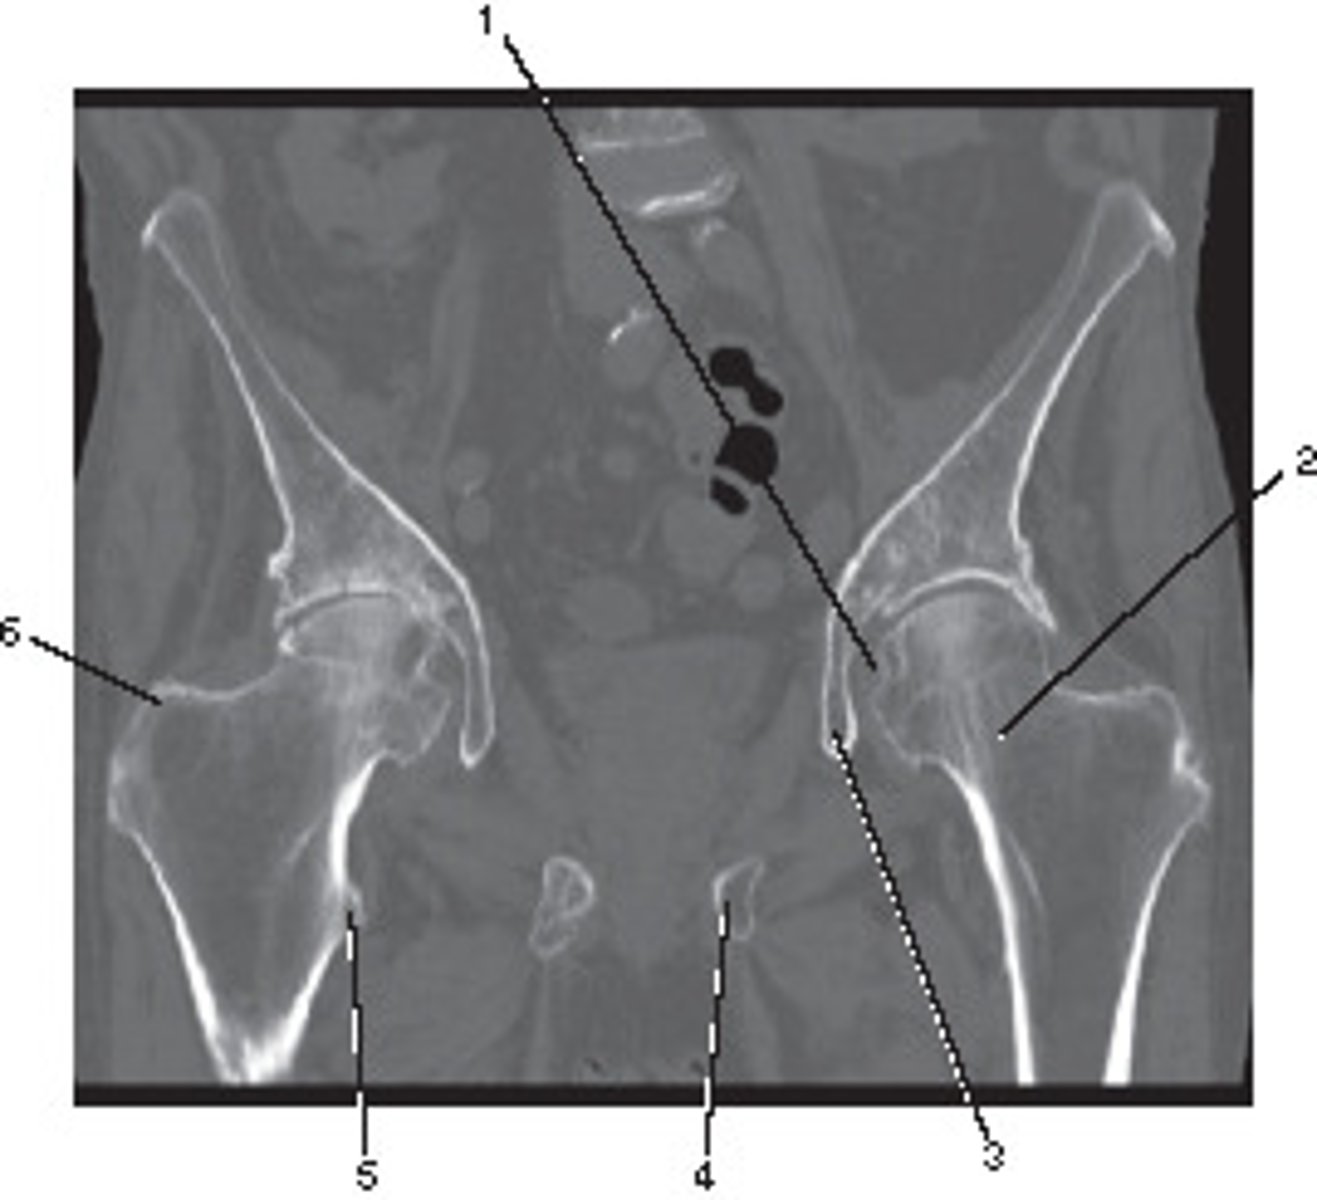

Number 2 corresponds to which of the following?

<p>Number 2 corresponds to which of the following?</p>

2

What number corresponds to the acetabulum?

<p>What number corresponds to the acetabulum?</p>

11